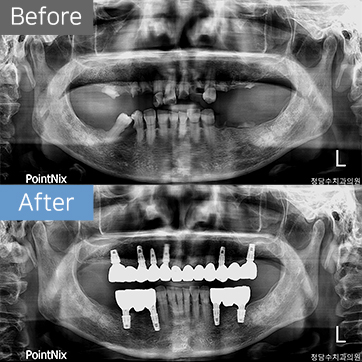

임플란트 50대여 임플란트

50대여 임플란트